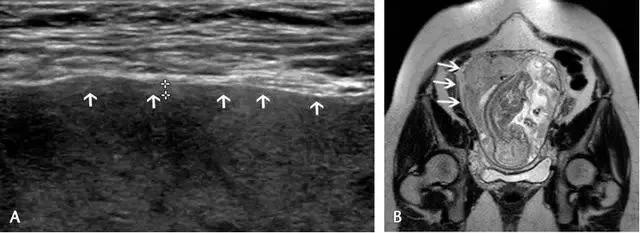

胎盘附着异常:包括胎盘粘连、胎盘植入及胎盘穿透(图 11)。胎盘粘连指胎盘策划向子宫肌壁延伸,但并未对其构成实质性的侵袭,占所有胎盘附着异常的75%。

胎盘植入指胎盘策划已侵入子宫肌壁,但并未突破浆膜层。穿透指不仅侵入肌壁,且已突破至浆膜层之外,可导致子宫的毗邻器官如膀胱、肠管及腹壁受累。超声是本病的主要显像方法,在临床高度怀疑本病或超声检查为阴性或不确定时,可使用 MRI(图 12 和图 13)。

图 11 为胎盘附着示意图 ,自最左图向右分别为正常、粘连、植入、穿透

图 12 示胎盘粘连:A 为孕 32 周患完全性前置胎盘(此图未显示)孕妇的子宫前壁横切面(线阵探头所得),可见肌壁由上至下、向膀胱子宫陷凹方向逐渐缺乏、变薄(短箭头所示)。B 为另一孕妇的冠状位 MRI,孕期经常性左腹痛,超声考虑胎盘粘连,长箭头示胎盘下方的低信号肌壁由左向右逐渐变薄。此 2 例均在剖腹产时被证实为胎盘粘连

图 13 示合并有完全性前置胎盘的胎盘穿透,患者有 2 次剖宫产病史:A 为子宫纵切面,箭头示肌壁逐渐变薄、子宫与膀胱之间的界限模糊,胎盘下的闲置空间消失(B :膀胱)。B 为同一患者的子宫矢状面,箭头示大量不规则紊乱血流向肌壁延伸。图 C 为另一孕妇 28 周时的矢状位 MRI,可见前次剖腹产瘢痕上缘存在胎盘对子宫前壁的侵犯、肌壁连续性局部中断(箭头)